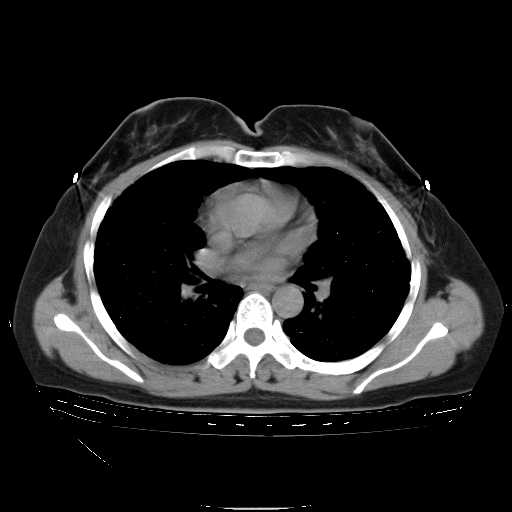

f50,肺ca治疗后,做过穿刺,确诊是肺ca,大家看看这是去年12月做的

考虑  腺癌肺内转移,治疗较前病灶缩小、减少

肺癌并肺内转移,这种疾病治疗后在影像上看略有好转,不是很显著,但是肿瘤治疗效果影像只是一方面。

支持肺癌并肺内淋巴管炎,  原发灶小了,但转移较前片明显了.

支气管血管束粗而乱,考虑肺癌肺内淋巴管转移,右侧乳房第一二层软组织成份较左侧多,不会有问题吧?

支持右肺下叶周围型肺癌并肺内淋巴管炎,  原发灶小了,但转移较前片明显了.。

标准的细支气管肺泡癌呀!治疗后病情有所控制,也没治愈的迹象!